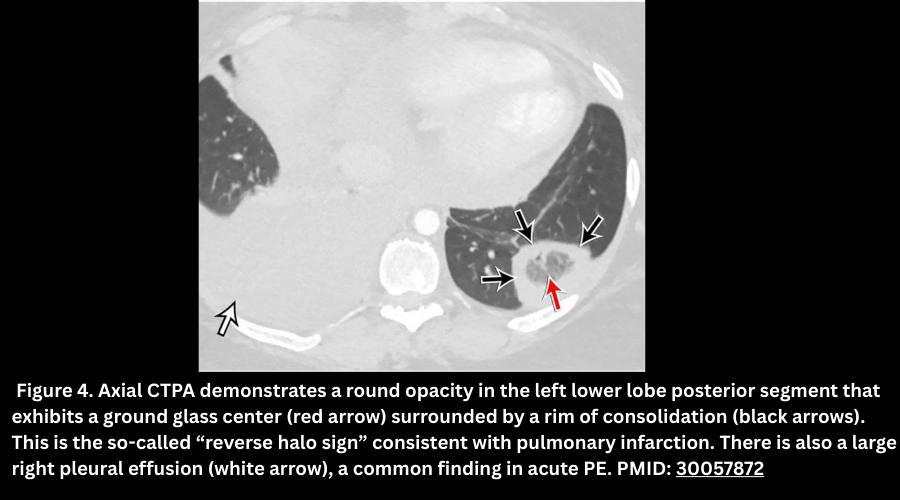

◾️Imaging Features of pulmonary infarction

- Anatomic distribution

- Classically, a pleural-based wedge-shaped opacity.

- However, it may involve the fissure or mediastinal pleura (so it may not always be wedge-shaped).

- Typically, in the lower lobes, multiple lesions may mimic multinodular disease.

- CT findings

- Consolidation (necrotic tissue).

- Ground-glass opacities (local hemorrhage).

- Reverse halo sign (rim of consolidation with central ground-glass).

- Cavitation (rare).

- Evolution: Over 3–5 weeks, infarcts shrink while remaining homogeneous → “melting ice cube sign.”

- Pulmonary infarcts appear as a peripheral opacity, heterogeneous enhancement, and may show the reverse halo sign (rim consolidation with central ground glass). Figure 4.